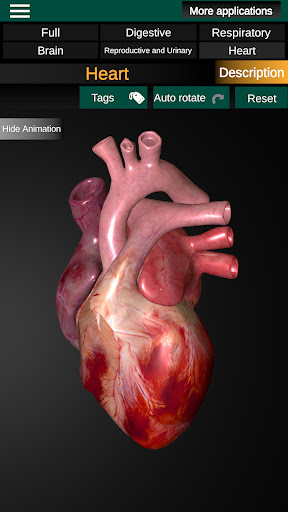

* Серце, що включає передсердя, шлуночки, аорту і одушевлення цього органу.